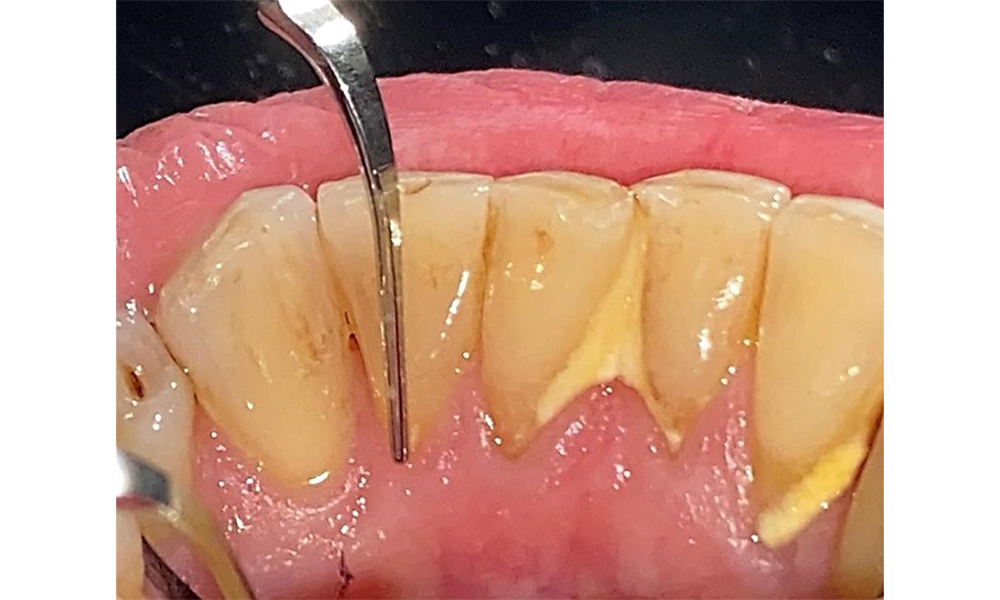

Probing to document the findings in tooth 27 mesiopalatal.

Fig. 8: Probing to document the findings in tooth 27 mesiopalatal. © Dr R. Krapf

The documentation of periodontal findings, including pocket depth probing and bleeding status, is mandatory during each dental appointment due to the presence of periodontitis (Fig. 8). This will record the individual therapeutic needs and facilitate a rapid response to any progression of the pre-existing periodontitis.

There are no limitations regarding the choice of instrumentation methods. Regular supragingival and subgingival instrumentation is essential to prevent disease progression due to the pre-existing periodontitis and high risk of recurrence. There are no limitations placed on the selection of instruments for mechanical biofilm removal from a general medical perspective, and removal should be performed as needed. Hard and mineralized plaque, such as calculus and concretions, should be removed using manual instruments or sonic/ultrasonic scalers (Fig. 9) (8, 9).